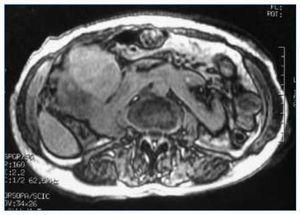

Describimos el caso de una mujer de 69 años con antecedentes de hipotiroidismo y riñón en herradura, sobre el que asienta un hipernefroma (fig. 1) pendiente de intervención, diagnosticado por otro servicio. Acude al servicio de urgencias por edemas y deterioro del estado general, siendo ingresada. En los análisis destaca: hemoglobina 11,4 g/dl, VCM normal, tiempos de coagulación alargados, creatinina 4,9 mg/dl, urea 142 mg/dl, proteínas totales 4,7 g/dl, calcio 8 mg/dl, acidosis metabólica moderada, proteinuria > 4 g/24 h, hematuria y leucocituria intensas.

Figura 1.